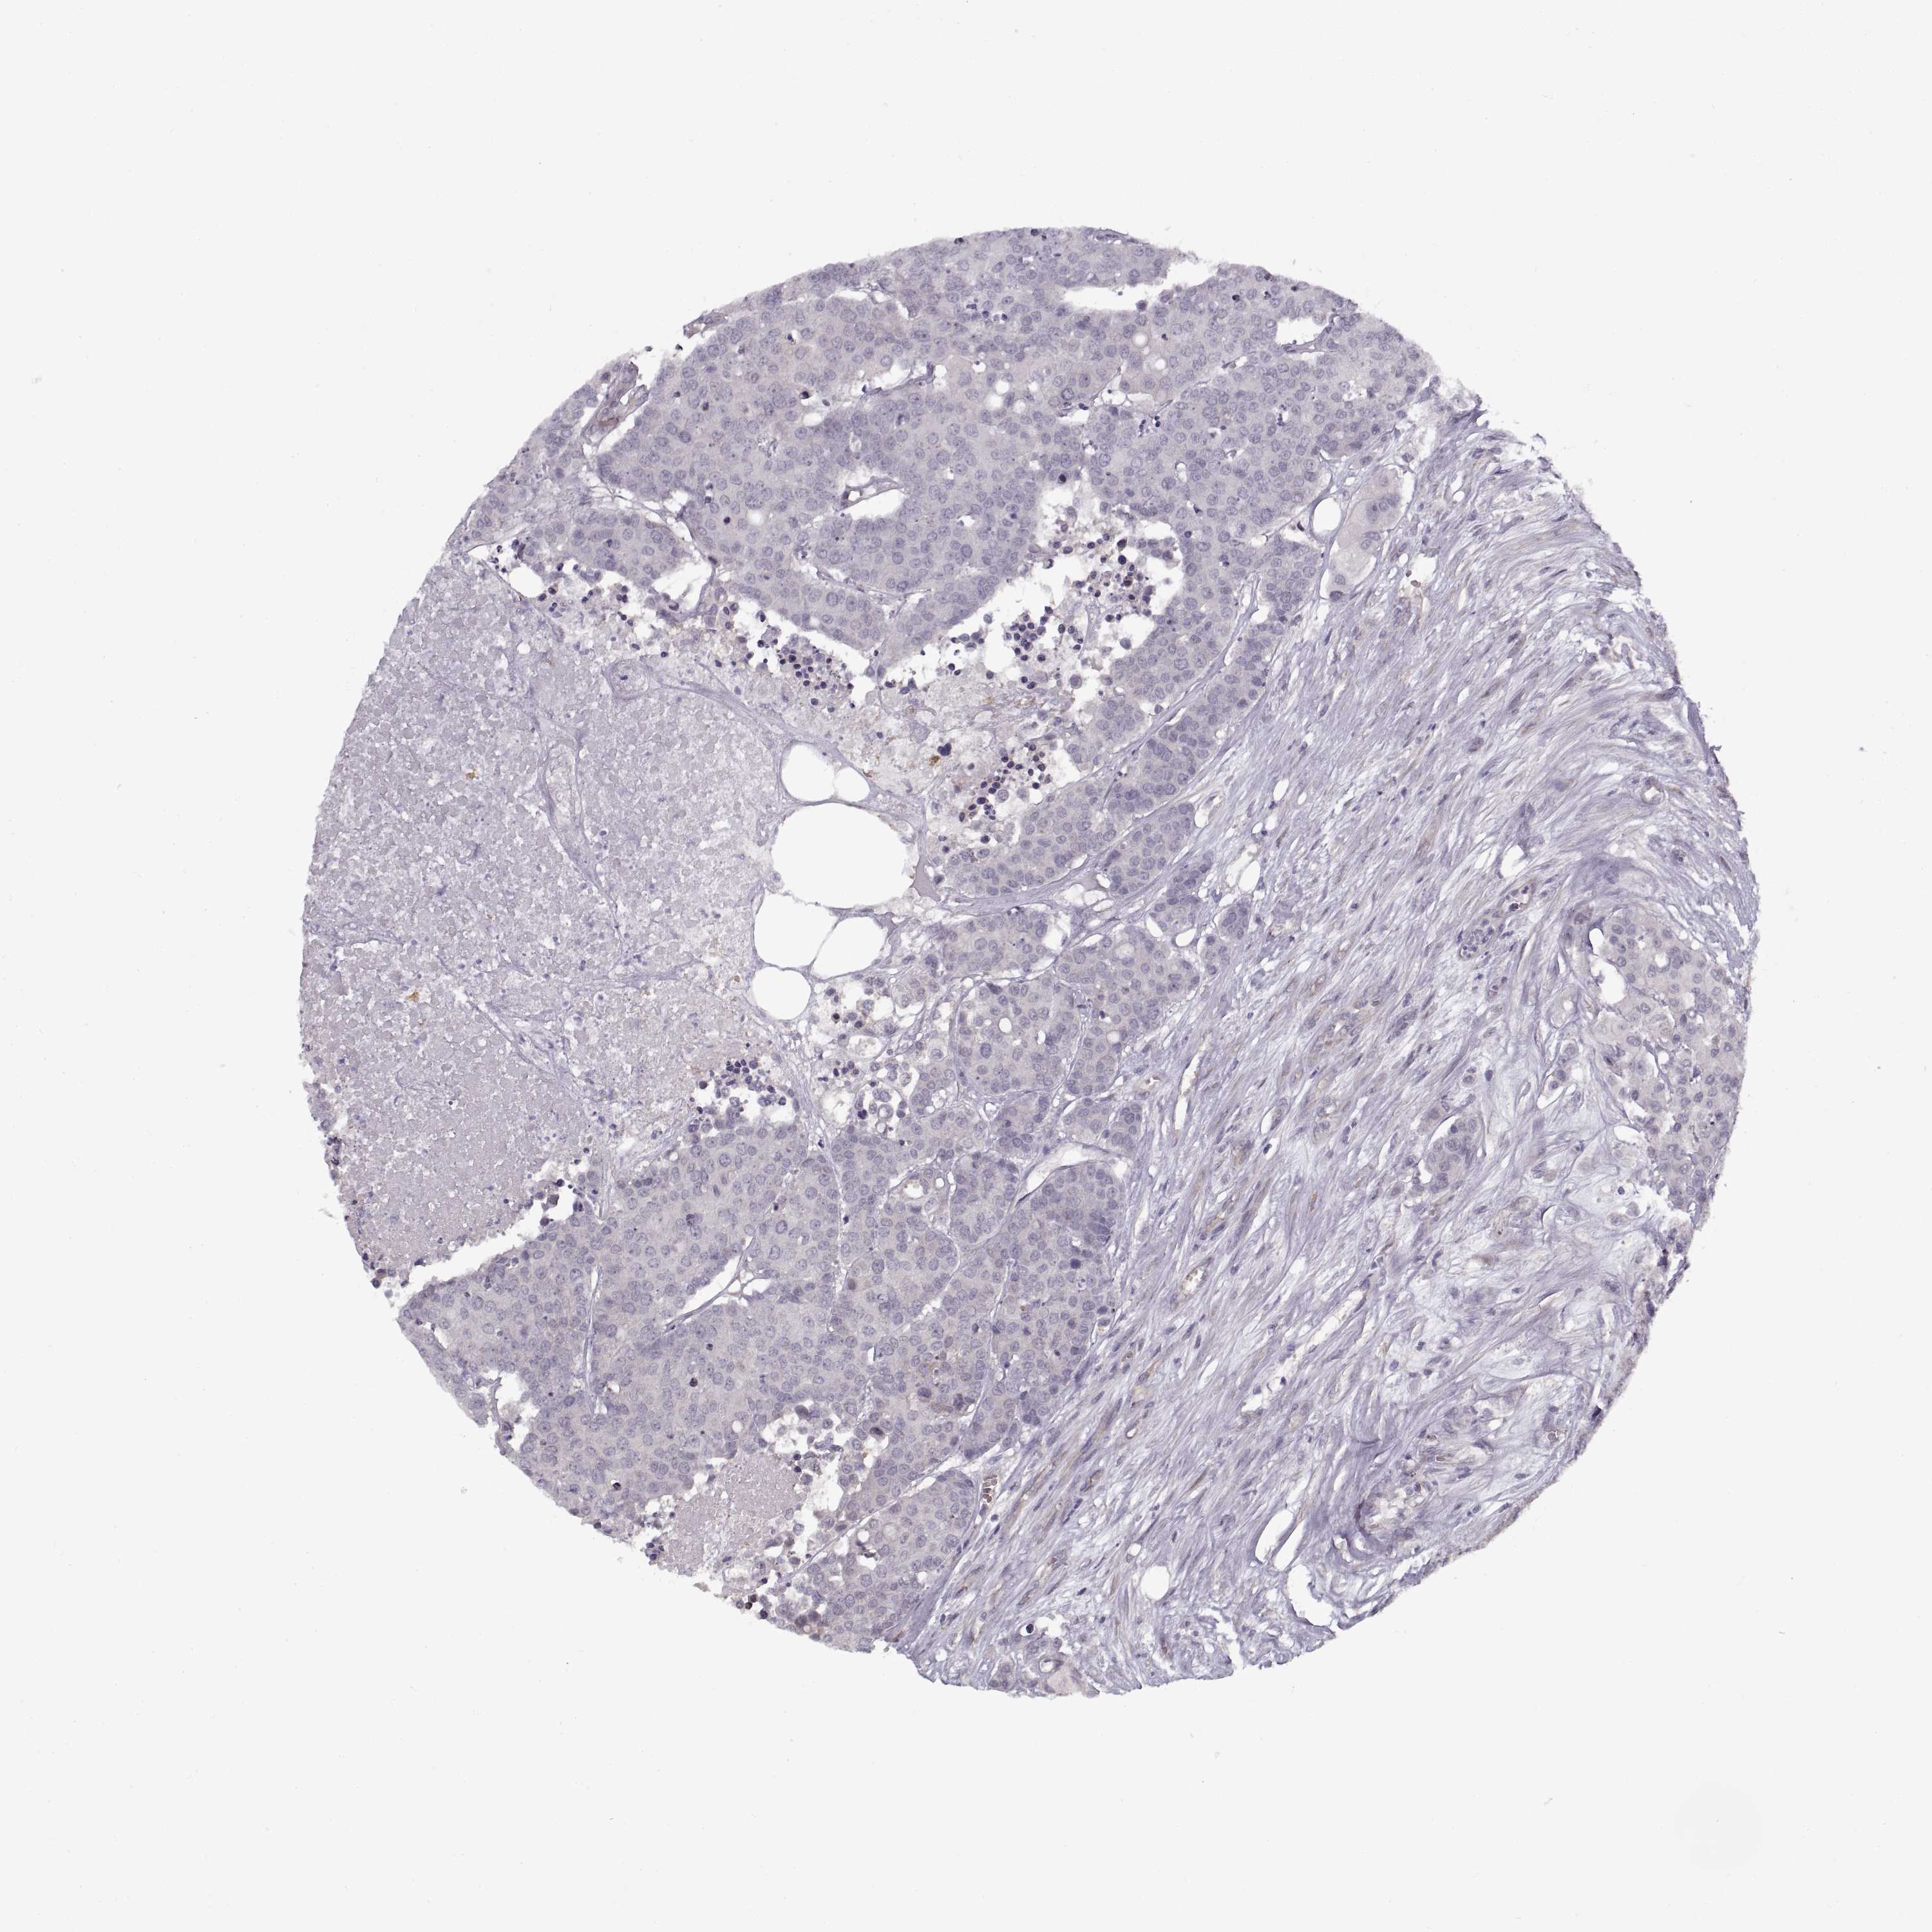

CARCINOID - Protein expressioni

A mouse-over function shows sample information and annotation data. Click on an image to view it in a full screen mode. Samples can be filtered based on level of antibody staining by selecting one or several of the following categories: high, medium, low and not detected. The assay and annotation is described here.

Antibody stainingi

Antibody staining in the annotated cell types in the current human tissue is reported as not detected, low, medium, or high, based on conventional immunohistochemistry profiling in selected tissues. This score is based on the combination of the staining intensity and fraction of stained cells.

Each image is clickable and will lead to virtual microscopy that enables deeper exploration of all samples and also displays staining intensity scores, fraction scores and subcellular localization as well as patient and tissue information for each sample.

Staining

High

Medium

Low

Not detected

Intensity

Strong

Moderate

Weak

Negative

Quantity

>75%

75%-25%

<25%

None

Location

Nuclear

Cytoplasmic/membranous

Cytoplasmic/membranous,nuclear

Carcinoid, malignant, NOS